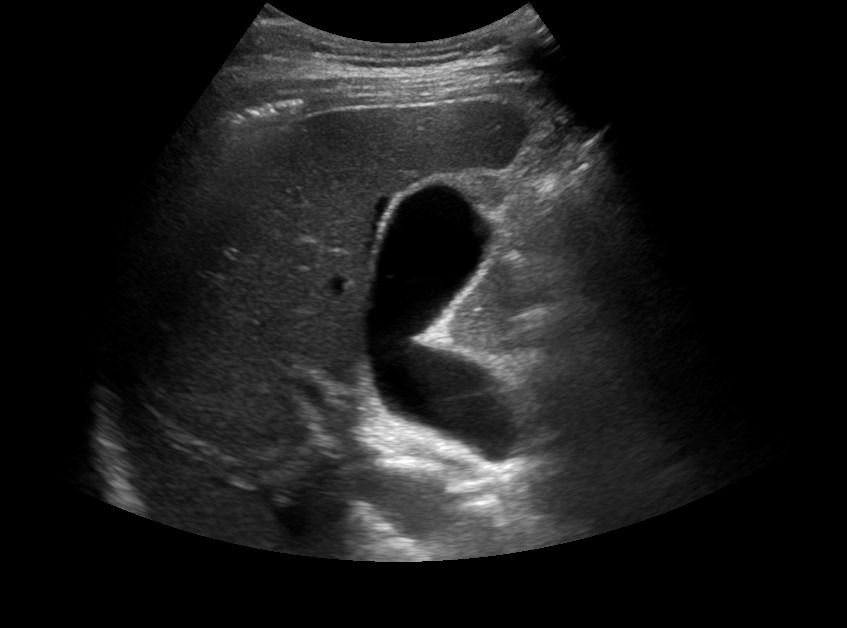

- Κυστικές αλλοιώσεις (κύστεις σε ήπαρ, νεφρούς, πάγκρεας)

- Συμπαγείς βλάβες όπως αιμαγγειώματα, αιμαγγειωμυολιπώματα, ή νεοπλάσματα στο ήπαρ, τους νεφρούς, και το πάγκρεας